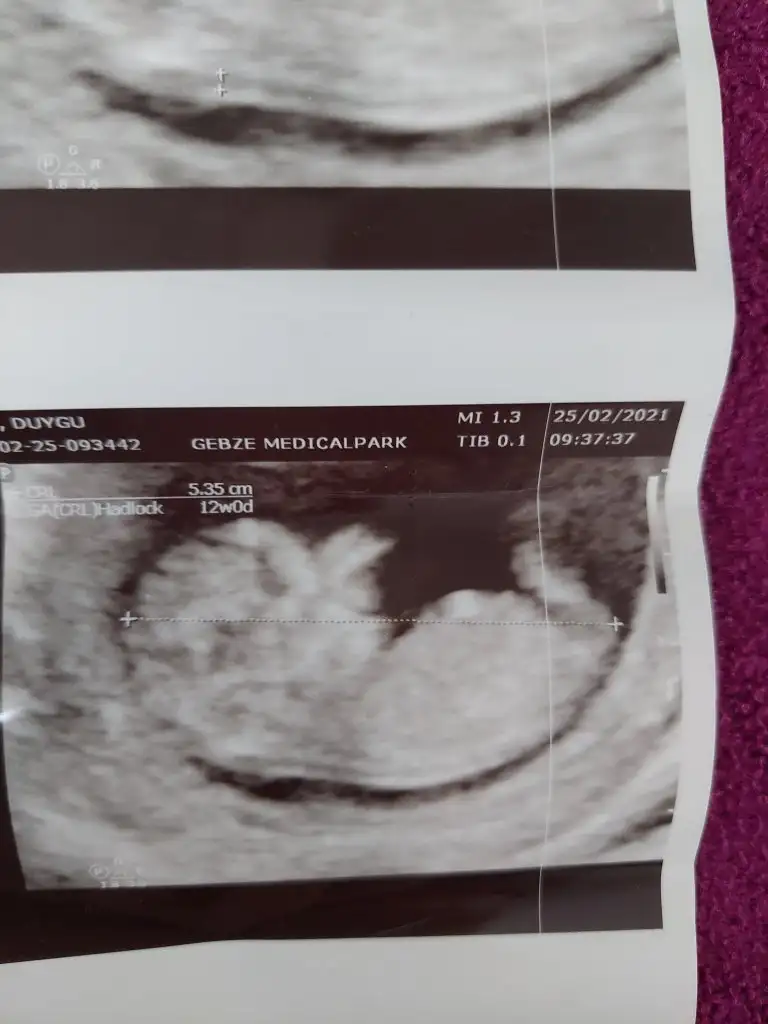

Net değil ama kız sanki başka USG varsa paylaşın 11 12 13 haftalar olmalıTahminlerinizi alabilirmiyim??? 12. Haftadan resim

Ben size yazmıştım kız dedim diğer konudaBana ısrarla bakmadınız 12 hafta karından![]()

Ben size yazmıştım kız dedim diğer konuda